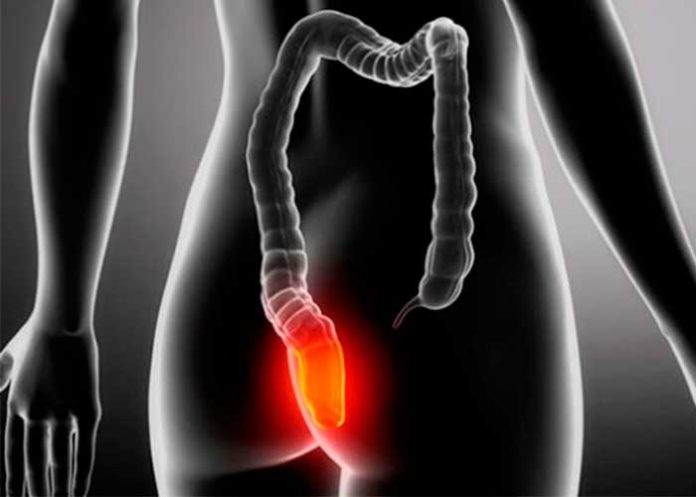

Las hemorroides son una enfermedad que ocurre como consecuencia de la dilatación de los vasos sanguíneos del ano y causa dolor, picazón y sangrados pero, ¿te imaginaste alguna vez que estar en el baño con tu teléfono podría causarlas?. Aunque parezca algo descabellado, esto podría pasar y aquí te explicamos

Internas: cuando ocurren dentro del ano.

Externas: cuando surgen en la abertura anal y se extienden fuera del ano, lo que se denomina prolapso hemorroidal. Si esta condición no se trata, puede resultar en la formación de coágulos y desencadenar un cuadro conocido como trombosis hemorroidal.

El Dr. Marcelo Averbach, coloproctólogo del Hospital Sírio Libanés de Brasil, llama la atención sobre un hábito bastante común y aparentemente inofensivo que está asociado al aumento de riesgo de desarrollar hemorroides: quedarse mucho rato en el inodoro usando el celular. Este hábito contribuye al surgimiento del cuadro porque permanecer en posiciones corporales que ejercen presión en el abdomen y el ano aumenta el riesgo de dilatación de las venas de la región (y, como consecuencia, causa hemorroides).